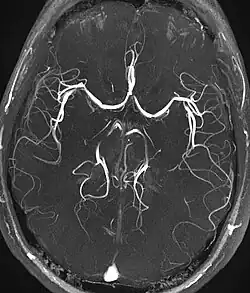

Pour l’angiographie par résonance magnétique (ARM en français et MRA en anglais ), le ToF est une méthode sous-jacente majeure. Dans cette méthode, le sang entrant dans la zone imagée n'est pas encore saturé, ce qui lui confère un signal beaucoup plus élevé lors de l'utilisation d'un temps d'écho court et d'une compensation de débit. Il peut ainsi être utilisé dans la détection d'anévrisme, de sténose ou de dissection[5].